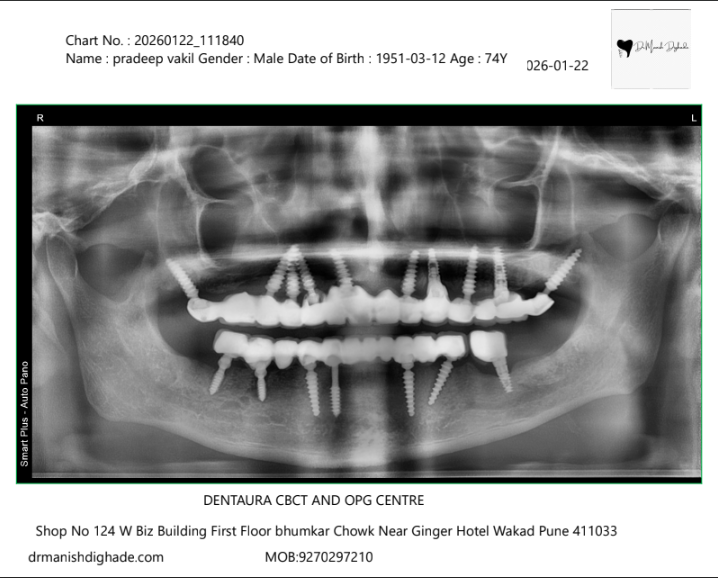

X-Ray Analysis

OPG — After

Radiographic Findings

The X-ray shows multiple implants placed in both the upper and lower jaws to support a full set of fixed teeth. These implants act as artificial roots and are strategically positioned to ensure proper stability and load distribution. This allows the patient to regain full chewing function and long-term durability.